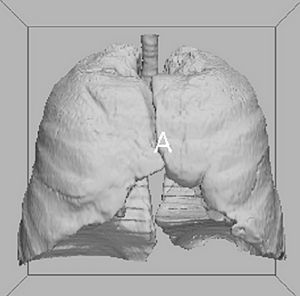

Images acquired with synchrotron-based PC-CT showing a rat small intestine that was decellularized via DET: (a) transverse cross section, (b) three-dimensional view. All scale bars represent 500 μm. Images were processed using the ESRF in-house software PyHST, and analyzed and displayed with ImageJ31 and 3D Slicer. |